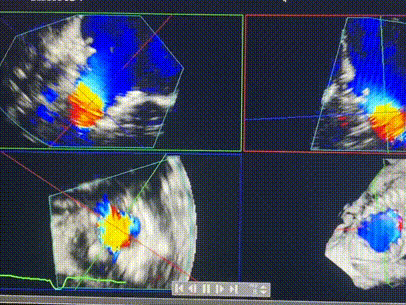

術(shù)后DSA顯示Lux-Valve Plus與Tendyne和ICD無相互影響

手術(shù)在全麻狀態(tài)下進行。術(shù)者采用經(jīng)右側(cè)頸靜脈入路的方式將輸送器送入患者心臟內(nèi),在TEE及DSA引導(dǎo)下調(diào)整輸送器頭端角度,使得輸送器與三尖瓣瓣環(huán)平面垂直。在輸送器進入右心室后釋放室間隔錨定裝置,而后釋放瓣葉夾持件(2個耳片結(jié)構(gòu))成垂直狀態(tài)。在TEE及DSA確定夾持件固定至三尖瓣葉根部且位于右室側(cè)后釋放人工瓣心房側(cè)盤片。隨后調(diào)整瓣膜同軸性以及室間隔錨定件位置(貼合室間隔),前推藏針管并固定,進而釋放室間隔錨定裝置,并再次確認瓣膜位置、穩(wěn)定性及同軸性,合攏輸送鞘后撤出輸送器,完成LuX-Valve Plus人工三尖瓣瓣膜的植入,僅殘余微量瓣周漏。且經(jīng)手術(shù)中心電生理團隊評估,病人的起搏器和ICD功能沒有受到影響。

LuX-Valve Plus經(jīng)血管三尖瓣置換系統(tǒng)此次“出海”圓滿完成,術(shù)后Rodrigo Estévez-Loureiro教授對LuX-Valve Plus經(jīng)血管三尖瓣置換系統(tǒng)的器械性能和治療效果大為稱贊,認為LuX-Valve Plus的手術(shù)體驗非常好。術(shù)后即刻超聲顯示三尖瓣反流幾乎完全消失,血流動力學(xué)改善顯著,患者恢復(fù)快。在面對復(fù)雜解剖結(jié)構(gòu)、超聲影像質(zhì)量不佳、有起搏導(dǎo)線干擾時,Lux-Valve Plus也體現(xiàn)了極強的適應(yīng)性。Thomas Modine教授和Anson Cheung教授也肯定了LuX-Valve Plus術(shù)中操作的便捷性,認為LuX-Valve Plus容錯率高,對術(shù)中影像的依賴較小,后期希望可以更多的應(yīng)用LuX-Valve Plus三尖瓣置換系統(tǒng)于臨床實踐,讓更多的三尖瓣重度反流患者盡早獲益,改善預(yù)后。